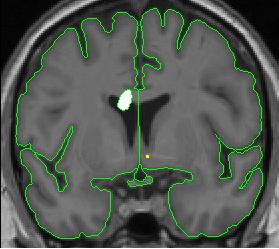

lateral ventricle 6

Part III - Posterior portion of lateral ventricle

Make sure the lateral ventricle is actually a ventricle, rather than a deep sulcus. To do this, look in other planes using the projection lines. There should be white matter between ventricle and the gray matter. Lateral ventricle can disappear for a few slices, and then re-appear.